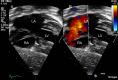

This review article will guide the reader through the basics of echocardiographic assessment of congenital left to right shunts in both paediatric and adult age groups. After reading this article, the reader will understand the pathology and clinical presentation of atrial septal defects (ASDs), ventricular septal defects (VSDs), atrioventricular septal defects (AVSDs) and patent arterial duct. Echocardiography is the mainstay in diagnosis and follow-up assessment of patients with congenital heart disease. This article will therefore describe the echocardiographic appearances of each lesion, and point the reader towards specific features to look for echocardiographically.